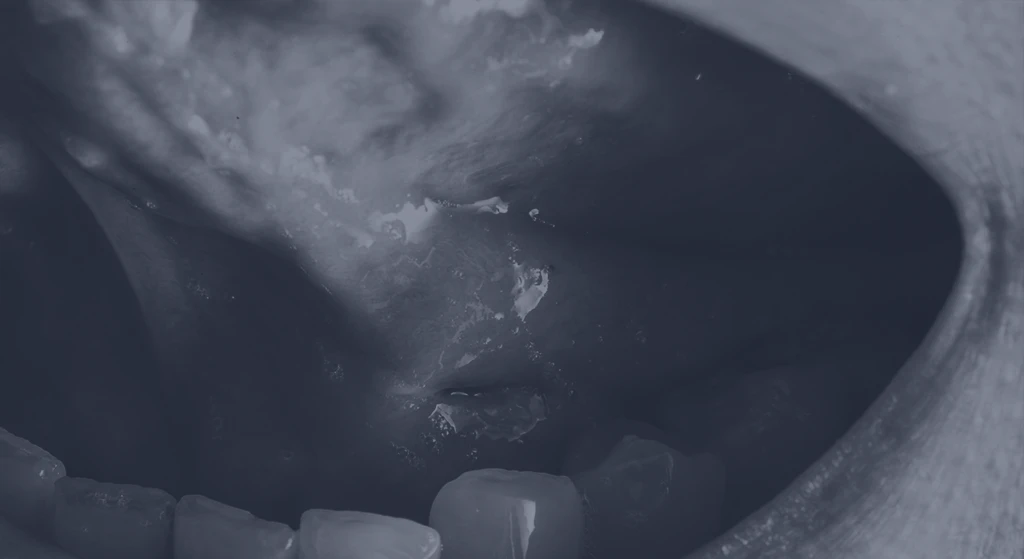

Um espaço seguro, estruturado e preparado para oferecer o melhor em cuidado especializado em Cirurgia de Cabeça e Pescoço.